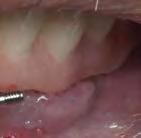

BTI Biotechnology Institute Tel: (+34) 945 140 024 | info@bticomercial.com | bti-biotechnologyinstitute.es • Carga inmediata en maxilares atróficos. • Mayor predictibilidad y menor morbilidad para el paciente. • Mayor aceptación de tratamientos. ACORTA TUS TRATAMIENTOS CON SOLUCIONES BTI www.bti-biotechnologyinstitute.com IMPLANTES CORTOS BTI DESDE SÓLO 4,5 mm. Radiografía a los 9 años